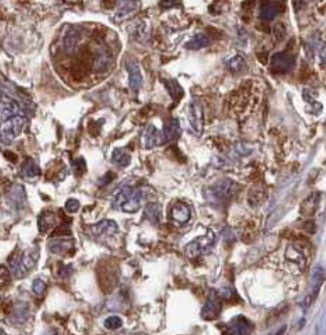

| 验证图片 | Immunohistochemistry of paraffin-embedded ovary tumor tissue FNab01271(CARD8 Antibody) at dilution of 1:50 |